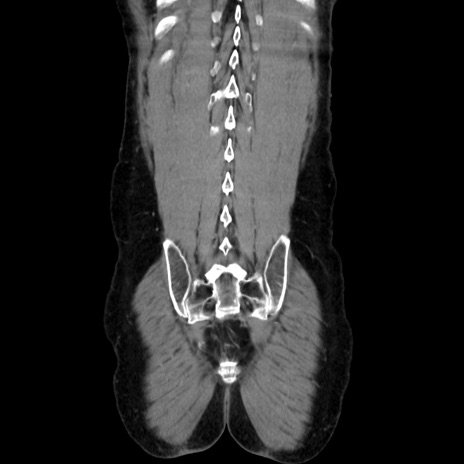

症例37(冠状断像)

【症例】40歳代 男性

【主訴】腹痛

【現病歴】4時間ほど前に電車に乗車中に臍部上より腹痛出現。徐々に増悪し起立困難となり、救急外来受診。生ものは数日食べていない。今朝お雑煮を食べた。

【身体所見】BT 36.8℃、BP 117/84mmHg、HR 91/min、SpO2 97%、苦悶様、腹部:臍上部広範囲圧痛あり、反跳痛±

【データ】WBC 8100、CRP 0.03